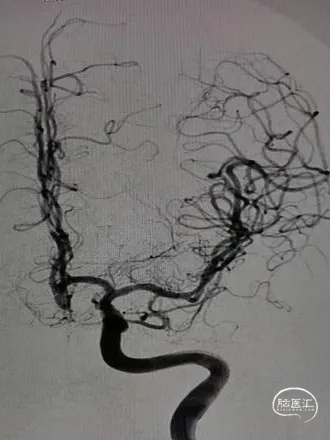

术前影像

栓塞过程

填塞第一枚Jasper®SS弹簧圈顺利;由于瘤囊较小,担心弹簧圈的稳定性,选择支架半释放后,顺利填入第2枚Jasper®SS弹簧圈。造影显示动脉瘤致密填塞,随后完全释放支架。

术后即刻影像